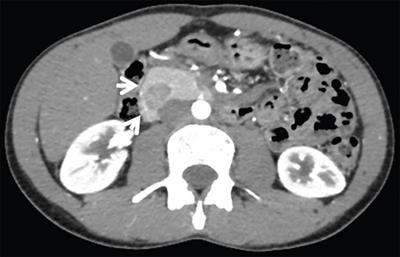

Image

Axial CECT image showing nodular accessory spleen (arrows) within the pancreatic tail having attenuation and enhancement similar to spleen on the arterial and the venous phase scans.